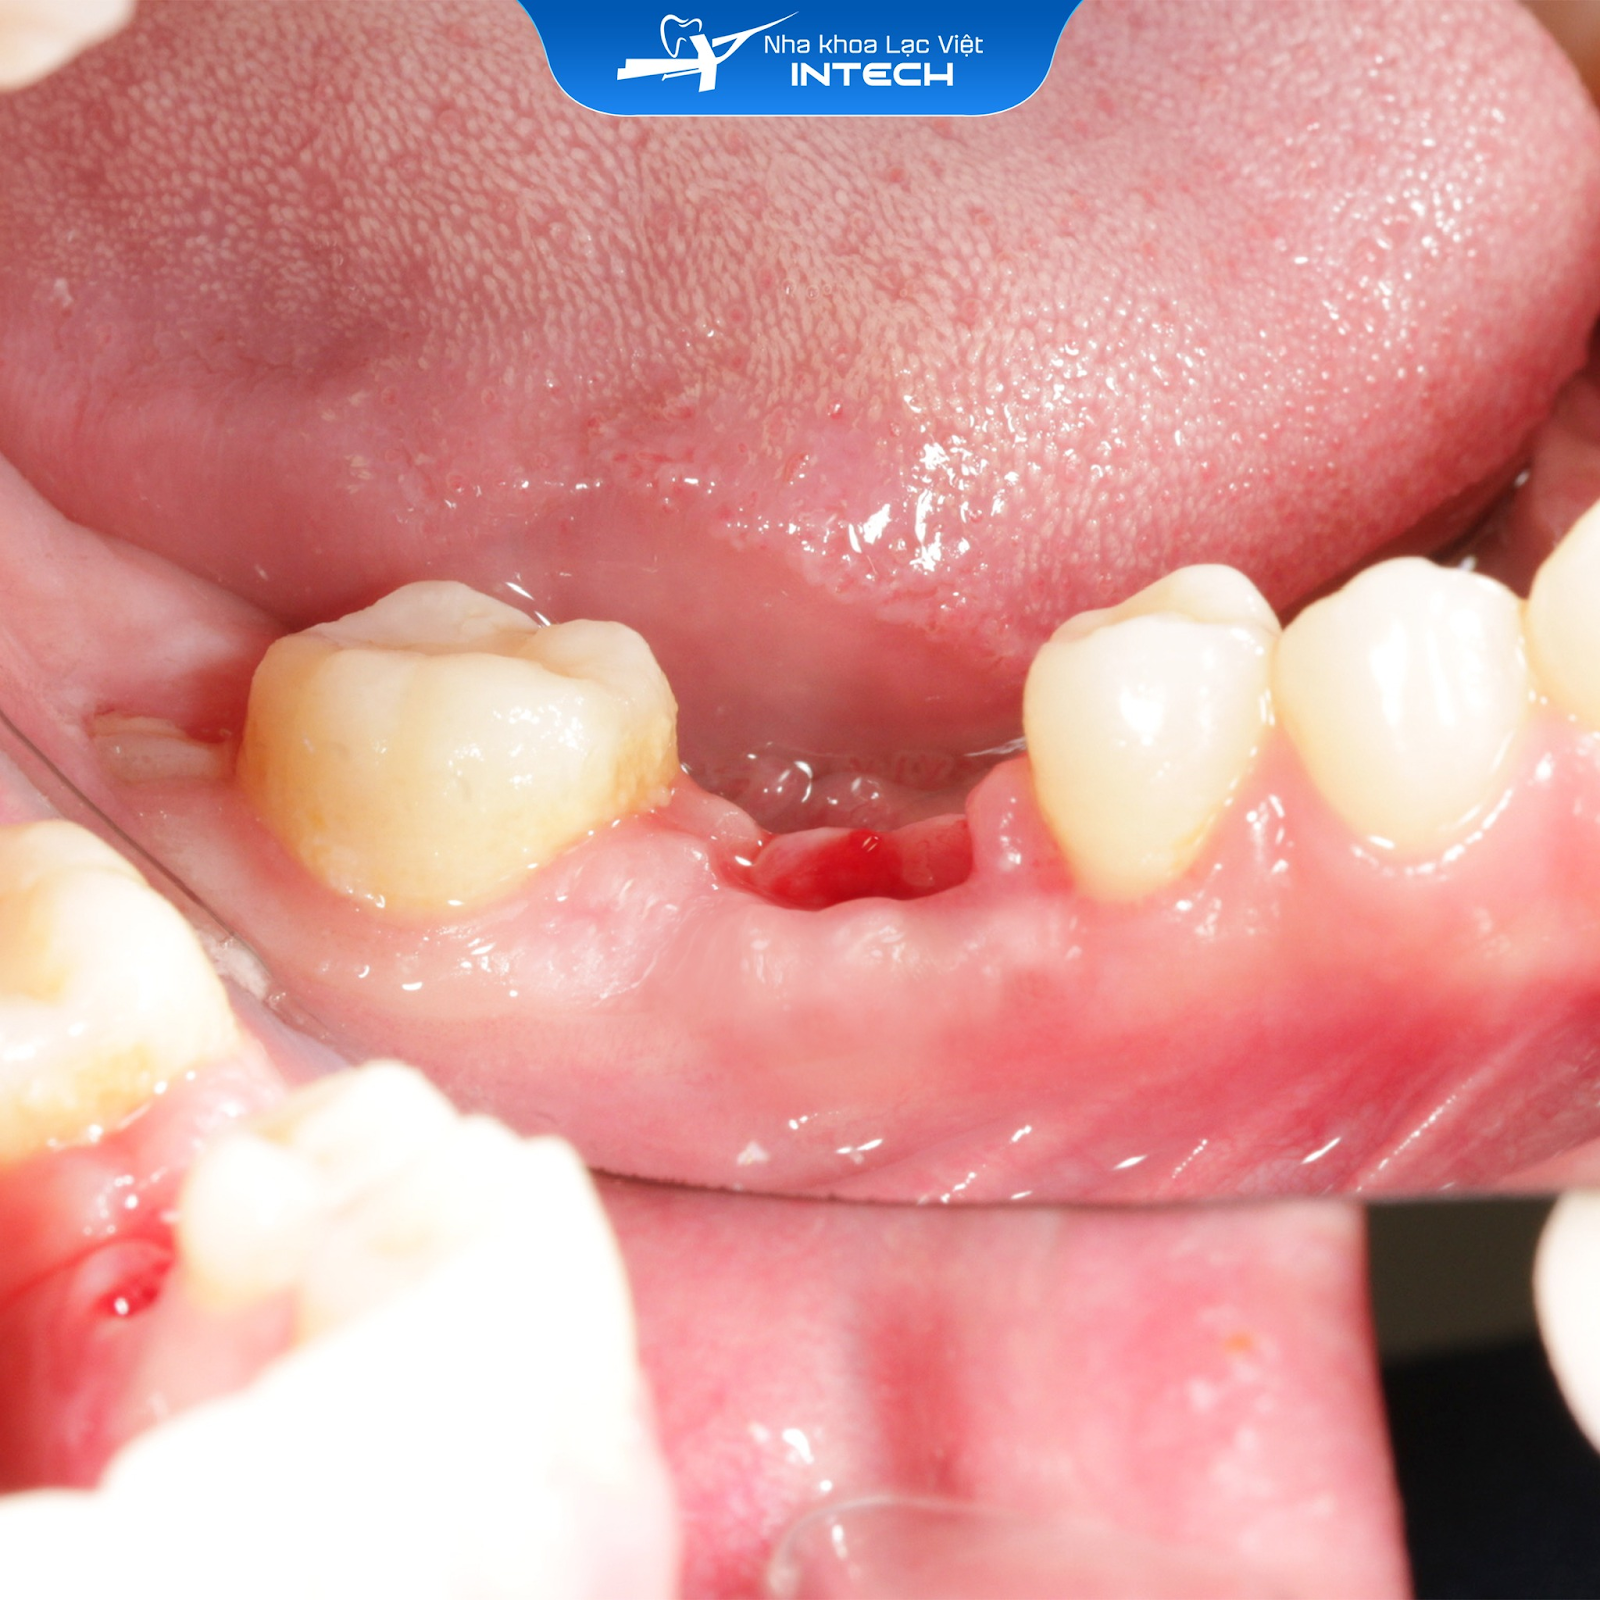

Ngoài ra, tại nha khoa Lạc Việt Intech, đội ngũ bác sĩ và cơ sở vật chất đảm bảo đủ điều kiện để thực hiện các phương pháp cấy ghép, thủ thuật phức tạp như cấy ghép tức thì, giải pháp phục hình cá nhân hóa DCT, ghép lợi...

Một ca phục hình cấy ghép Implant tức thì kết hợp ghép xương, được thực hiện đúng quy trình và đảm bảo an toàn tại Nha khoa Lạc Việt Intech

Thủ thuật ghép lợi trước khi cấy ghép Implant được thực hiện an toàn, chính xác tại nha khoa Lạc Việt Intech